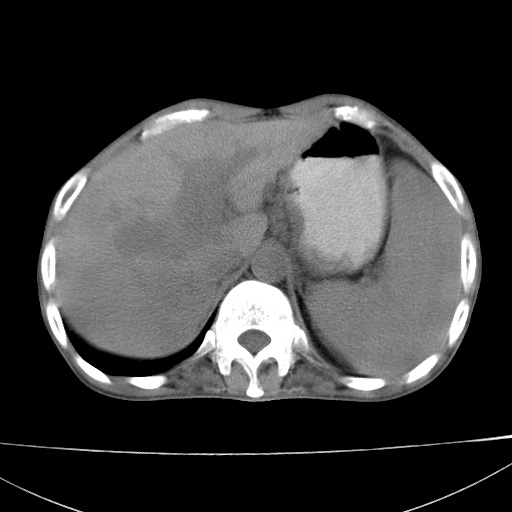

患者 男  41岁,右上腹痛伴腹泻10天,8年前有乙肝,本次b超查肝右叶占位来做ct ,请会诊!

肝硬化\\脾大\\门静脉高压,胃底静脉曲张可能性大.肝右叶肝癌肝内转移,建议增强.左侧小结石.

支持肝癌伴肝内转移,脾大,门静脉高压,胃底静脉曲张。

1)考虑肝癌;建议行ct增强扫描检查。2)脾大,门静脉高压,胃底静脉曲张。3)左肾小结石。

1)考虑肝癌及门脉瘤栓,建议行ct增强扫描检查。2)脾大,门静脉高压,胃底静脉曲张。3)左肾小结石。

结合病史;考虑肝癌。门静脉高压,脾大。胃底静脉曲张。

1)考虑肝癌;2)脾大,门静脉高压,胃底静脉曲张。3)左肾小结石。建议行ct增强扫描检查。